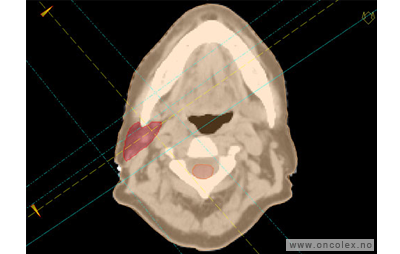

Målvolum

Skisse over hvordan strålefeltet planlegges:

• GTV (Gross Tumor Volume): Identifisert tumor.

• CTV (Clinical Target Volume) GTV + omkringliggende vev hvor det kan væremikroskopisk spredning.

• ITV (Internal Target Volume): CTV + en indre margin som tar hensyn tilindre bevegelser og endringer av CTV.

• PTV (Planning Target Volume): Innstillingsmargin som inneholder ITV og samtidig tar hensyn til antatte pasientbevegelser, samt variasjoner i pasientopplegging og feltinnstillinger.

• Feltgrense. Tegnes som oftest på kroppen.

ICRU (International Commission on Radiation Units and Measurements)